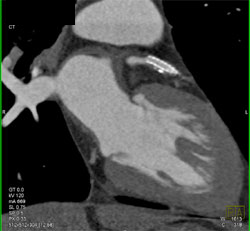

Patent Stent in LAD